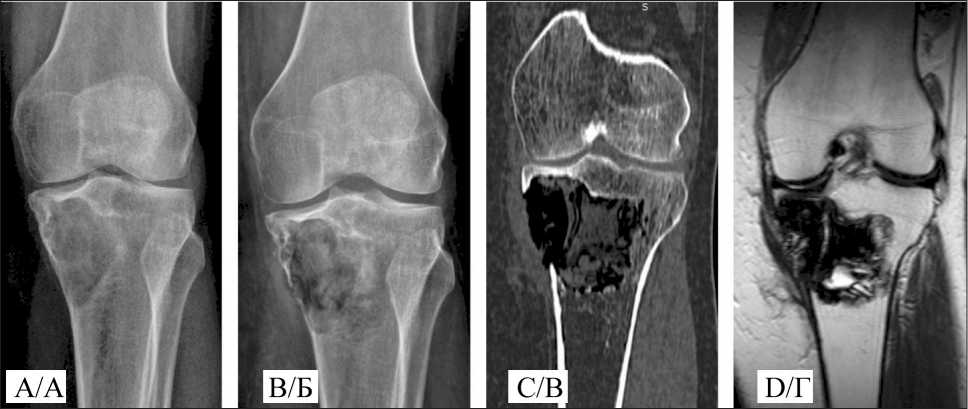

Fig. 3. A 49-year-old female patient. Giant cell tumor of the proximal tibia: A –pre-operative x-ray; B – post-operative x-ray;

C – post-operative CT; D – post-operative MRI. Note: created by the authors

Рис. 3. Пациентка O., 49 лет. Диагноз: Гигантоклеточная опухоль проксимального метадиафиза большеберцовой кости: А – рентгенограмма перед операцией; Б – послеоперационная рентгенограмма;

В – послеоперационная МСКТ; Г – послеоперационная МРТ. Примечание: рисунок выполнен авторами

room temperature, with no pronounced exothermic reaction; the polymerization time was 16–18 minutes. After the material ceased expanding and its structure became compacted, the wound was closed layer by layer. In all cases, the cortical plate maintained its integrity, as confirmed by radiographic examination.

Postoperative care was standard. Patients received antibacterial prophylaxis and dressings. Wound healing occurred by primary intention without signs of inflammation. Sutures were removed 1.5–2 weeks postoperatively. External immobilization was not applied. Patients were mobilized from the first day, with verticalization on the second day. Joint mobility exercises began on days 2–3, with partial weight-bearing resuming two weeks after surgery. Radiographic examination of the surgical site was performed two days postoperatively. The maximum postoperative hospital stay was 14 days, with an average of three days. Local control was assessed by dynamic observation and imaging studies. The radiographic invisibility of the material complicates monitoring of cavity filling, necessitating supplementary imaging such as MRI and CT (Fig. 3).